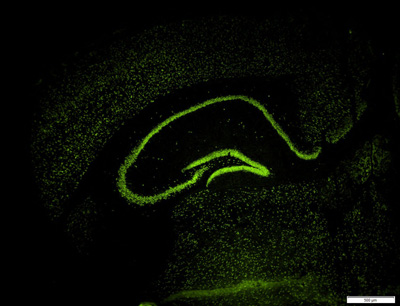

Singewald and his team used a special mouse strain (129S1/SvlmJ) which they had previously identified together with the US brain researcher Andrew Holmes. Like anxiety patients, these mice exhibit a reduced capacity for fear extinction and are therefore an ideal model for identifying cellular and molecular mechanisms that can promote anxiety therapy. In fact, the researchers found that increased acetylation of histones promotes fear extinction in these mice, thus establishing a clear relationship between epigenetic modifications and the correction of impaired extinction. In further convincing experiments, the group then identified cellular and molecular processes that contribute to this mechanism.